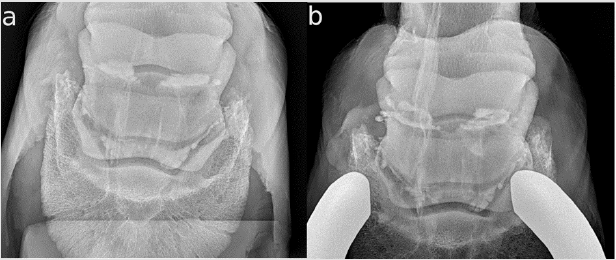

Horse 11 has a chronic right front limb lameness (3/5). The distal digital nerve block was positive. The radiographs and ultrasound of the tendon in the heel region (not transcuneal) were without significant findings. The owners reported a history of stumbling. Because they did not want to make an MRI, the NB was injected and the additional CE views were obtained. There were several longitudinal (proximo-distal) straight and radiopaque lines in the DPr-PaDiO CE (Figure 3a). The horse was diagnosed with a DDFT tendonitis. Additionally, there was an irregular proximal border of the dye column. The horse was given a poor prognosis for riding but a guarded prognosis for a pasture retirement. A special shoe for DDFT tendonitis was advised. The horse was sound for two months and returned with recurrent lameness after three months. The suspected tendon tear had enlarged enormously (Figure 3b) and was not visible in the ultrasound of the pastern region. The prognosis given was now poor. A neurectomy was performed even with the assessment that the chance was very poor and the tendon tear would be progressive. Three months later the horse was euthanized because of lameness when walking.

Figure 3: CE X-rays of horse 11, right front, lateral is to the left;

a. DPr-PaDiO CE view from May 28, 2019; there are several longitudinal (proximo-distal) straight radiopaque lines at the level

of the NB. These lines were identified as dorsal DDFT lesions. The proximal border is very narrow to the proximal end of the

navicular bone This seems to be a adhesion between the CSL and DDFT.

b. DPr-PaDiO CE view from August 21, 2019; the same findings as in a) but the lateral lesion of the DDFT has become much

larger, reaching proximally an area where it could be easily seen in ultrasonography.